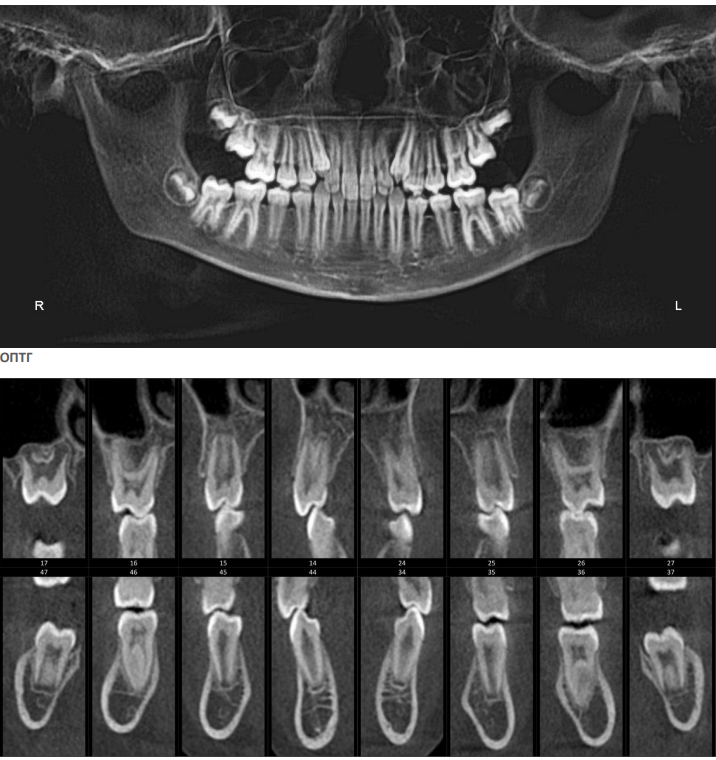

На КЛКТ определяются зачатки вторых и третьих моляров на верхней и нижней челюсти, степень формирования которых соответствует возрасту и полу. Невысокое положение клыков с увеличенной мезиальной ангуляцией.

На ТРГ головы в боковой проекции - ретроположение верхней и нижней челюсти в сагиттальном направлении без нарушения размеров апикальных базисов и их взаиморасположения. Тип роста – нейтральный. Дентоальвеолярный анализ характеризует изменение инклинации резцов на верхней и нижней челюсти с незначительным дентоальвеолярным удлинением. На нижней челюсти в области боковой группы зубов определяется зубоальвеолярное укорочение, что характеризует формирование глубокой кривой Spee на данном этапе формирования прикуса постоянных зубов. (рис.3.)

Рис. 3. КЛКТ и ТРГ головы в боковой проекции пациента А. до лечения.

Рис.10. КТ челюстей, характеризующая нормальные параметры апикальных базисов челюстей в трансверзальном направлении с правильным расположением по инклинации моляров верхней и нижней челюсти.